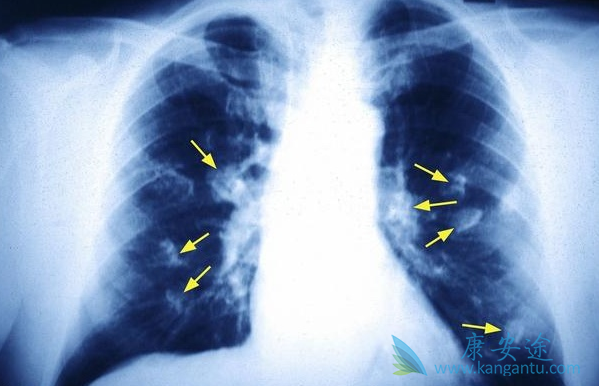

声音嘶哑是肺癌晚期患者最常见症状。控制左侧发音功能的喉返神经由颈部下行至胸部,绕过心脏的大血管返行向上至喉,从而支配发音器官的左侧。因此,若肿瘤侵及纵隔左侧,使喉返神经受到压迫,声嘶便产生了,但却无咽痛及上呼吸道感染的其它症状。有发生区域性扩散的肺癌晚期患者几乎都有不同程度的气促。